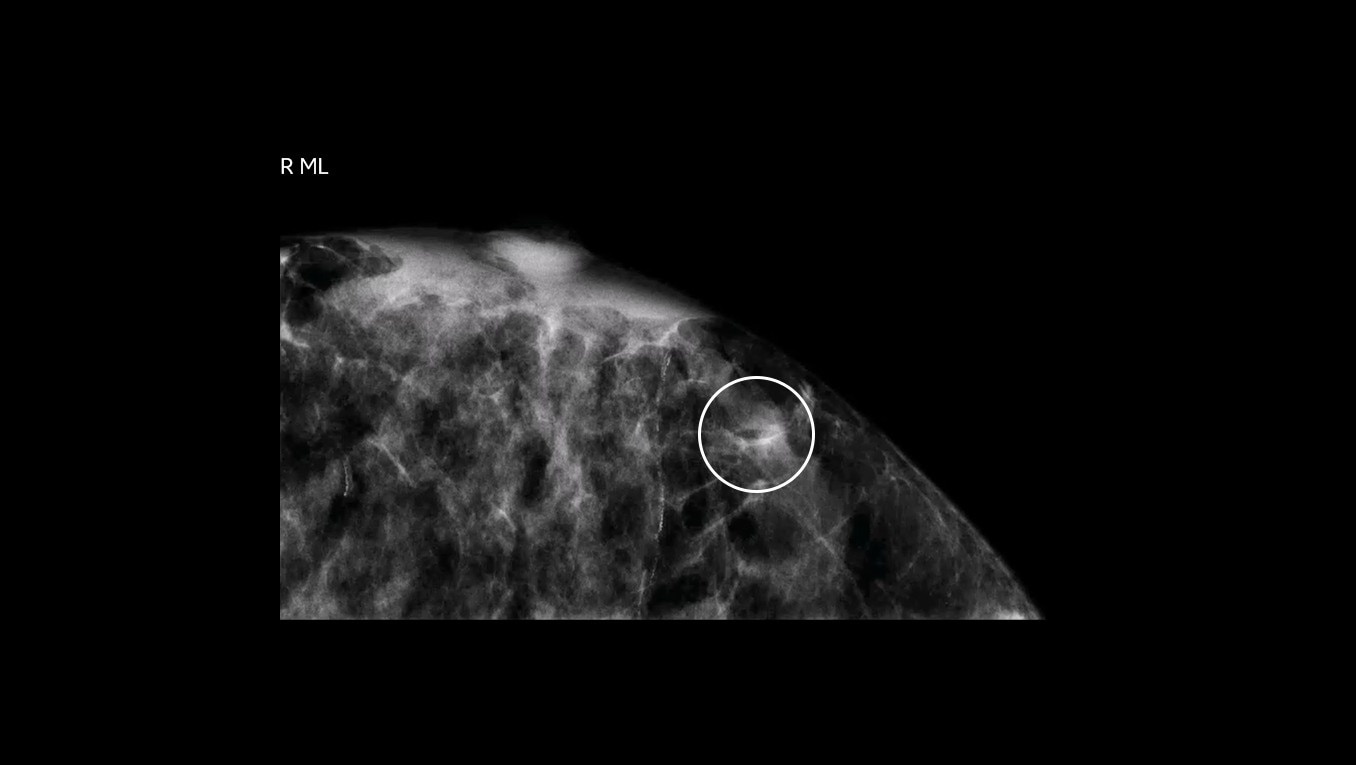

See and biopsy what matters

Serena Bright enables providers to see lesions using contrast-enhanced mammography (CEM) and sample with certainty. This allows patients to undergo breast biopsy exams using the same mammography equipment, in a familiar setting, with familiar staff, to help relieve some of the stress of a biopsy procedure.

Avoid the challenges of seeking correlating lesions in MRI. CEM allows you to see lesions clearly and sample with certainty with the same image guidance.

Clarity with complementary imaging

Compare like to like for increased biopsy correlation

With high sensitivity and specificity, CEM helps drive accuracy in biopsy. It allows you to clearly target suspicious areas by correlating lesion locations already identified in your patient’s diagnostic enhanced mammogram.